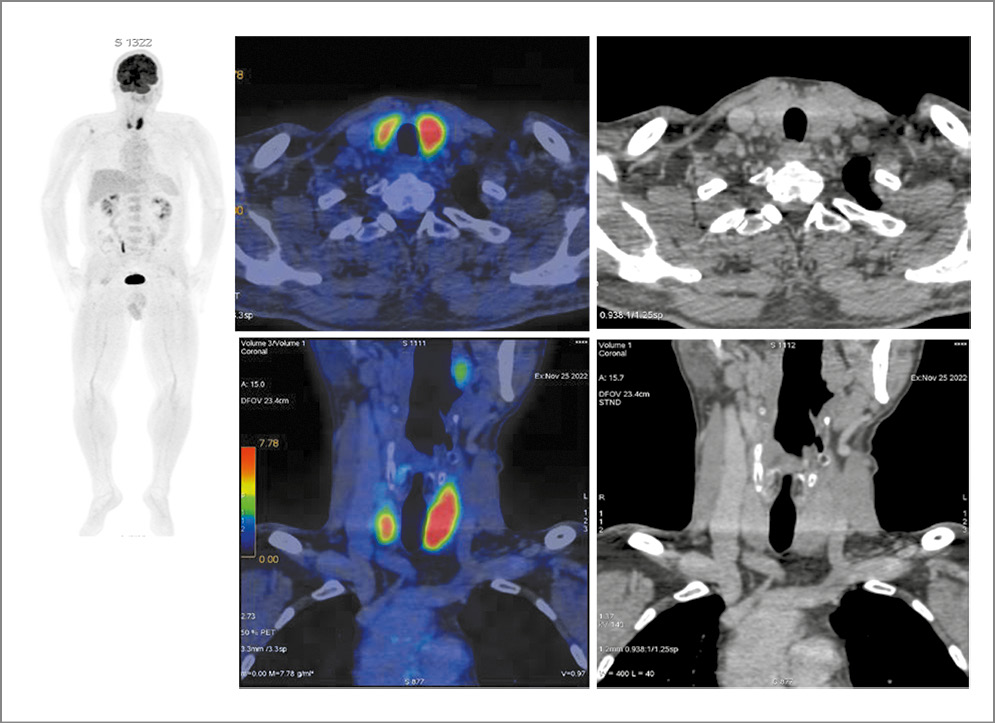

Выполнена ПЭТ/КТ с 18-ФДГ. Выявлено увеличение размеров обеих долей: левой – до 28×19 мм, правой – до 26×16 мм с диффузной гиперфиксацией РФП SUVmax 10,55. Лимфоузлы шеи не увеличены, метаболически неактивные (рис. 1).

Рис. 1. Больной Н., 61 год. На MIP ПЭТ, аксиальных, корональных КТ и ПЭТ/КТ-проекциях отмечается диффузное увеличение размеров обеих долей щитовидной железы: левой – до 28×19 мм, правой – до 26×16 мм, с диффузной гиперфиксацией РФП, SUVmax 10,55. С четкими ровными контурами, однородной структуры. Патологических образований в области мягких тканей шеи не выявлено.